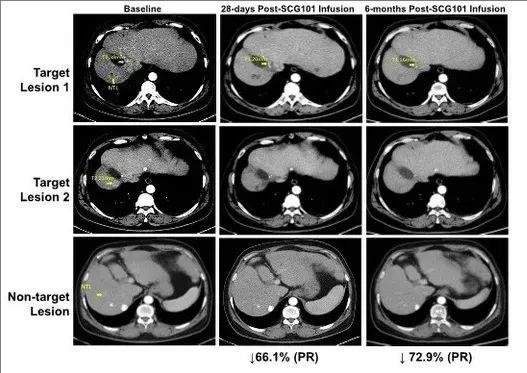

2、肿瘤缓解:患者在治疗第28天,达到部分缓解(PR),肿瘤靶病灶较基线时缩小66%;在治疗第4个月时,肿瘤靶病灶进一步缩小74.5%;更为惊喜的是,另一处病灶完全消失。截至数据统计时止,该患者仍处于持续缓解状态,肿瘤已超过6.9个月未进展!

图3 患者回输SCG101前后的影像学变化